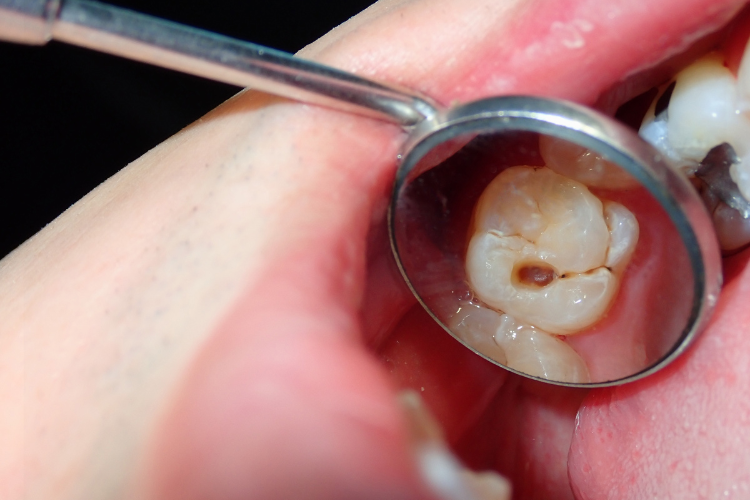

Identifying potential issues in their early stages allows for prompt intervention and treatment.

Composite fillings are popular because they can be closely matched to the color of natural teeth, providing a more aesthetically pleasing result